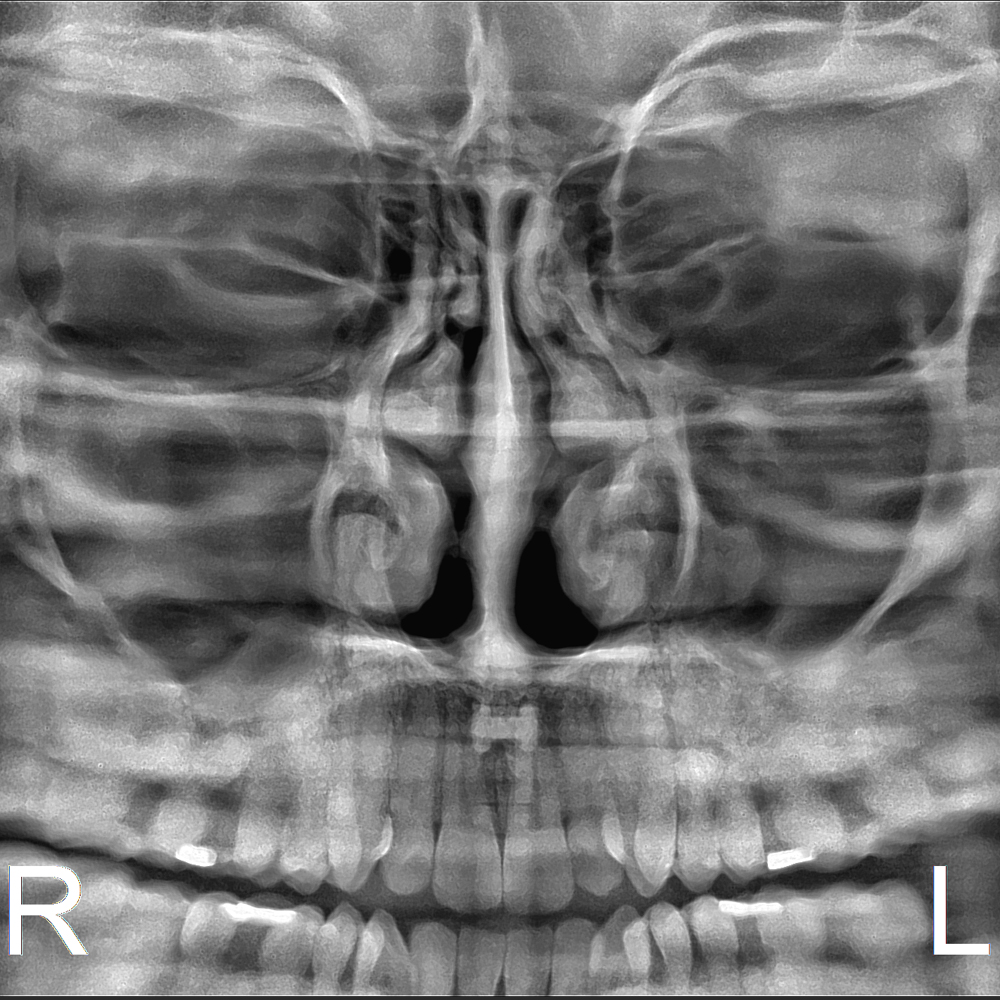

y todos los exámenes en el perfil cefalométrico (Posteroanterior, Antero-posterior, 45 Grados, Lateral, Carpal, PA de Walters, Axial Bazal, Hirtz).